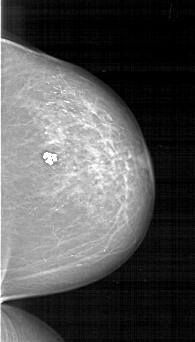

A_1276_1.LEFT_CC

LEFT_CC LINES 5746 PIXELS_PER_LINE 3541 BITS_PER_PIXEL 12 RESOLUTION 43.5 OVERLAY

FILE: A_1276_1.LEFT_CC.OVERLAY

TOTAL_ABNORMALITIES 1

ABNORMALITY 1

LESION_TYPE CALCIFICATION TYPE PLEOMORPHIC DISTRIBUTION CLUSTERED

ASSESSMENT 4

SUBTLETY 4

PATHOLOGY BENIGN

TOTAL_OUTLINES 1

BOUNDARY